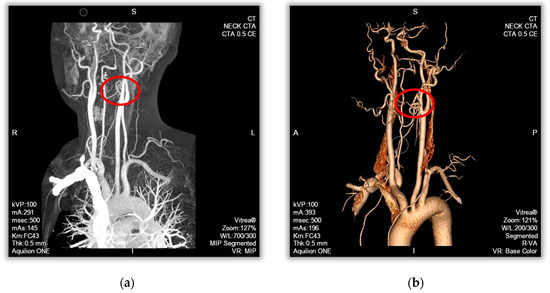

The 3D reconstruction process of the mathematical model was performed as follows. The 2D-image DICOM file of CT tomography was imported into the image processing software Mimics Medical (Version No. 20.0). According to differences in the grayscale thresholds of different tissues, the target vessels were filtered and isolated using threshold segmentation and regional growth functions to obtain the 3D model. Then, the reconstructed model was imported into the 3D forward engineering software, 3-Matic, for smoothing and optimization of the inlet and outlet cross-sections to obtain a computational model of the fluid domain (blood). The fluid domain model was imported into the Geometry module of ANSYS software (Version No. 19.0) for constructing the vessel wall. A complete vessel model was then obtained. Finally, the vascular model was imported into the CFD software (ANSYS 19.0) for fluid–structure interaction calculation, and the calculated results were analyzed for hemodynamics, as shown in Figure 1a.

The cases were selected by intercepting a carotid artery with a length of 40 mm and a normal portion with a diameter of approximately 5 mm at one of the most atherosclerotic sites, which were reconstructed in three dimensions. The vessel stenosis rate of the narrowest part in the continuous flatten atheromatous plaque of the lesioned vessels was 40%, and the vessel stenosis rate of the narrowest part in the protruding atheromatous plaque of the lesioned vessels was 70%, as shown in Figure 1b.

Figure 1. Carotid artery medical imaging and 3D imaging. (a) CT image. (b) Angiographic stereoscopic imaging.